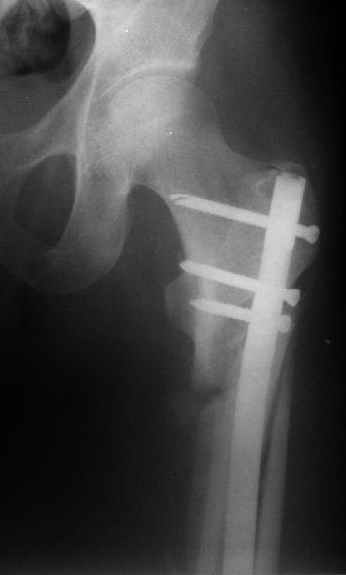

В частности, на проксимальном конце сделано еще одно дополнительное статическое отверстие. Можно ввести в проксимальном отделе 4 винта, из них 3 статические (2 в круглые отверстия и 1 по нижнему краю овального). Картинки в приложении. На дистальном конце стержня тоже кое-что улучшено. Спрашивайте в аптеках, как говорится. Выпускается предприятием "ЦИТО" (Москва), то есть это малобюджетное решение.

Конечно, мы не синтезируем остеопорозые вертельные переломы согласно прилагаемому примеру, винты 6 мм вырежутся. Но у более молодых при хорошем качестве кости такие или подобные гвозди с поперечным расположением винтов вполне применимы для меж- и подвертельных переломов.

Это было года 2,5 назад, мы тогда еще уточняли возможности шинирования с угловой стабильностью гвоздем с поперечным расположением винтов при переломах проксимального отдела бедра. Пациенту не пришлось приобретать намного более дорогой рекон или проксимальный гвоздь. В приложении еще несколько примеров применения того гвоздя при высоких переломах бедра, в том числе с более латеральной точкой входа. Гвоздь изгибаем для этого.